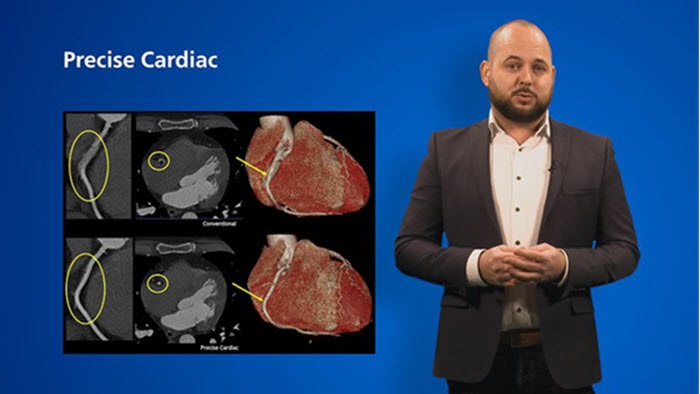

Spotlight on: Cardiac CT (Spectral CT 7500)

See beyond routine cardiac imaging with the additional clinical information of Spectral CT for advanced cardiac applications. Learn how the Spectral CT 7500's "Always On" Spectral CT workflow helps you meet the needs of all your patients with zero compromises.

Spectral CT 7500

Unlock the full potential of CT as a non-invasive cardiac diagnostic tool.